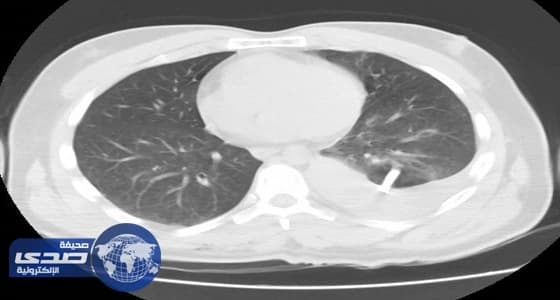

أنقذ فريق طبى بمستشفى الأمير متعب بن عبدالعزيز في سكاكا بالجوف، حياة مريض أربعيني، واستخراج شظايا زجاجية من رئة المريض؛ وذلك إثر سقوطه على طاولة زجاجية، مما تسبب في اختراق قطع وشظايا زجاجية للجدار الصدرى للمريض واختراق بعضها للرئة اليسرى، مما أدى إلى تمزقات بالرئة اليسرى، واسترواح هوائي دموي.

وقام الفريق الطبي بعمل عملية جراحية واستخرج الشظايا الزجاجية ، وخرج المريض من المستشفى بعد تماثله للشفاء.